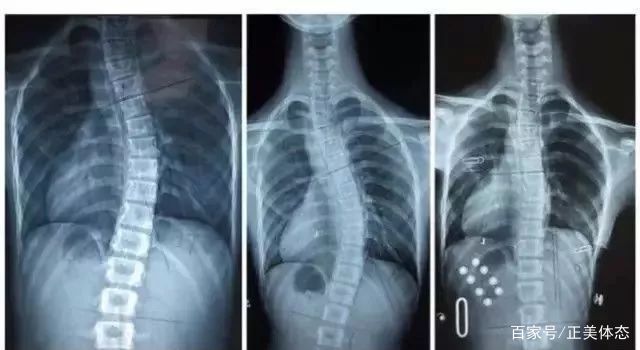

图中为一例胸右腰左S型脊柱侧弯侧弯

这个时候应拍摄站立位的全脊柱X线片,如果正位X线片显示脊柱有大于10度的侧方弯曲,即可判断为脊柱侧弯。